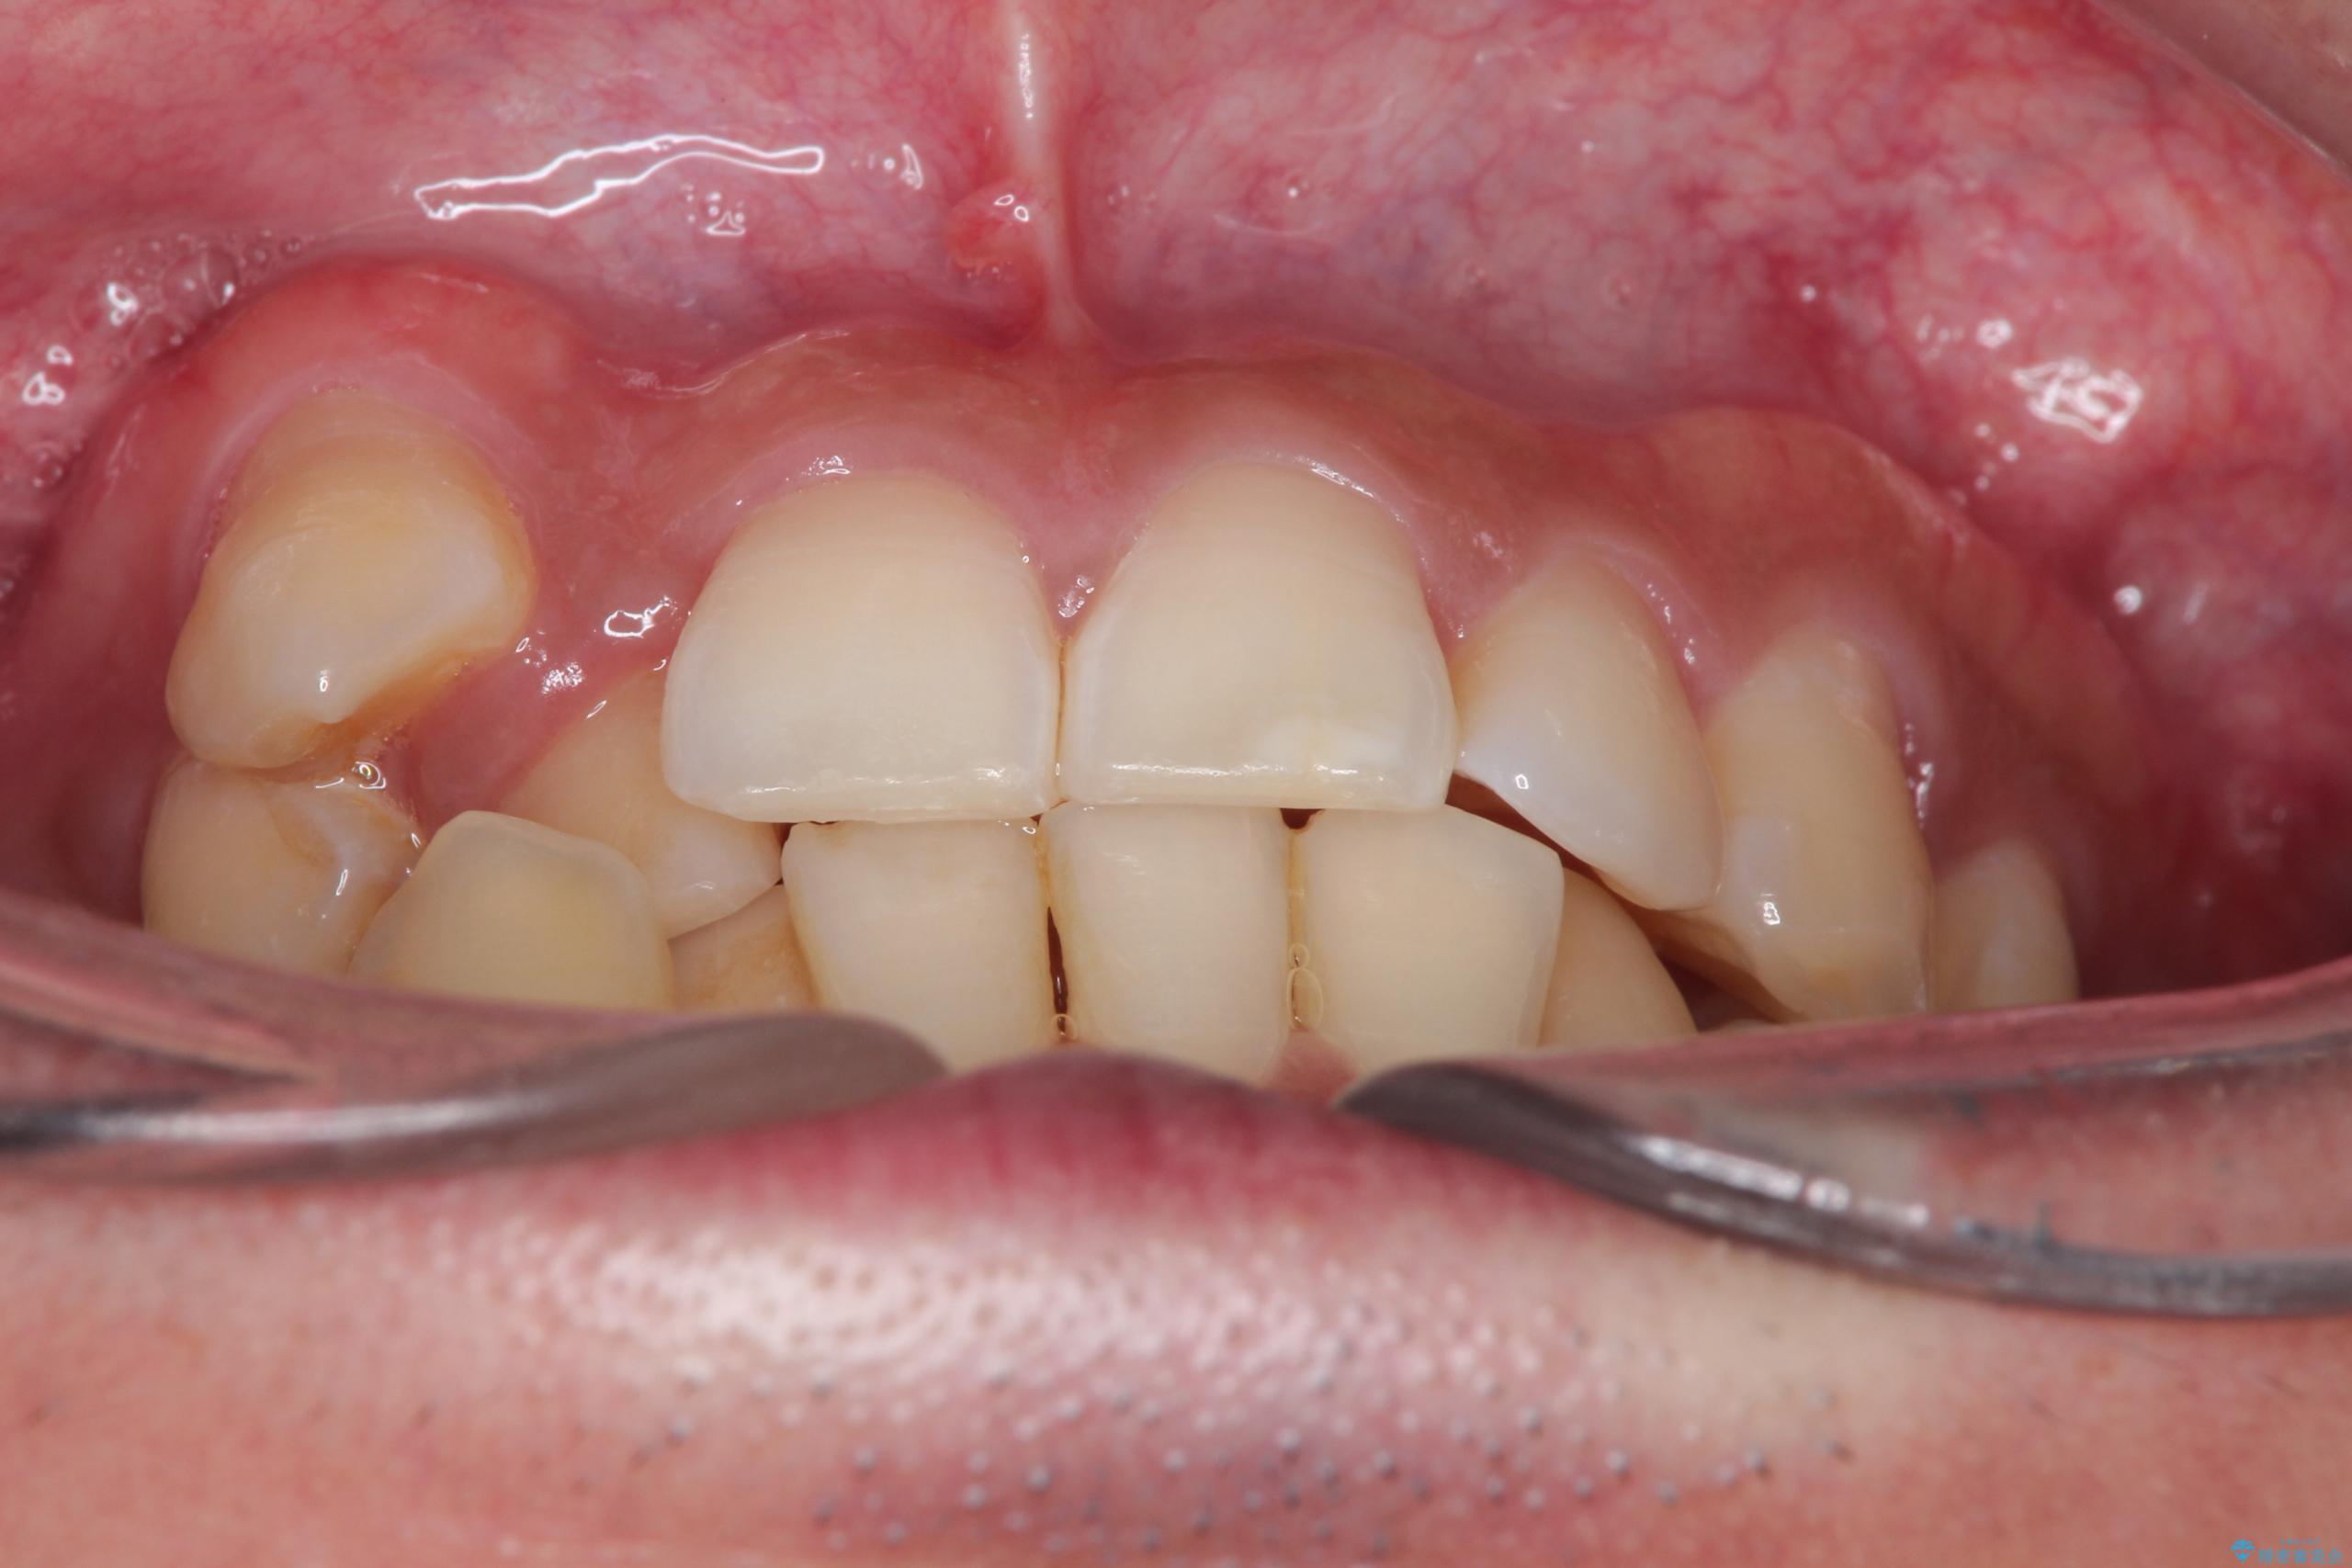

- 主訴:右上の八重歯と、下の歯の凸凹を治したい

右側2級、左側1関係だったため、右側上下第一小臼歯を抜歯し、ワイヤー矯正を行いました。